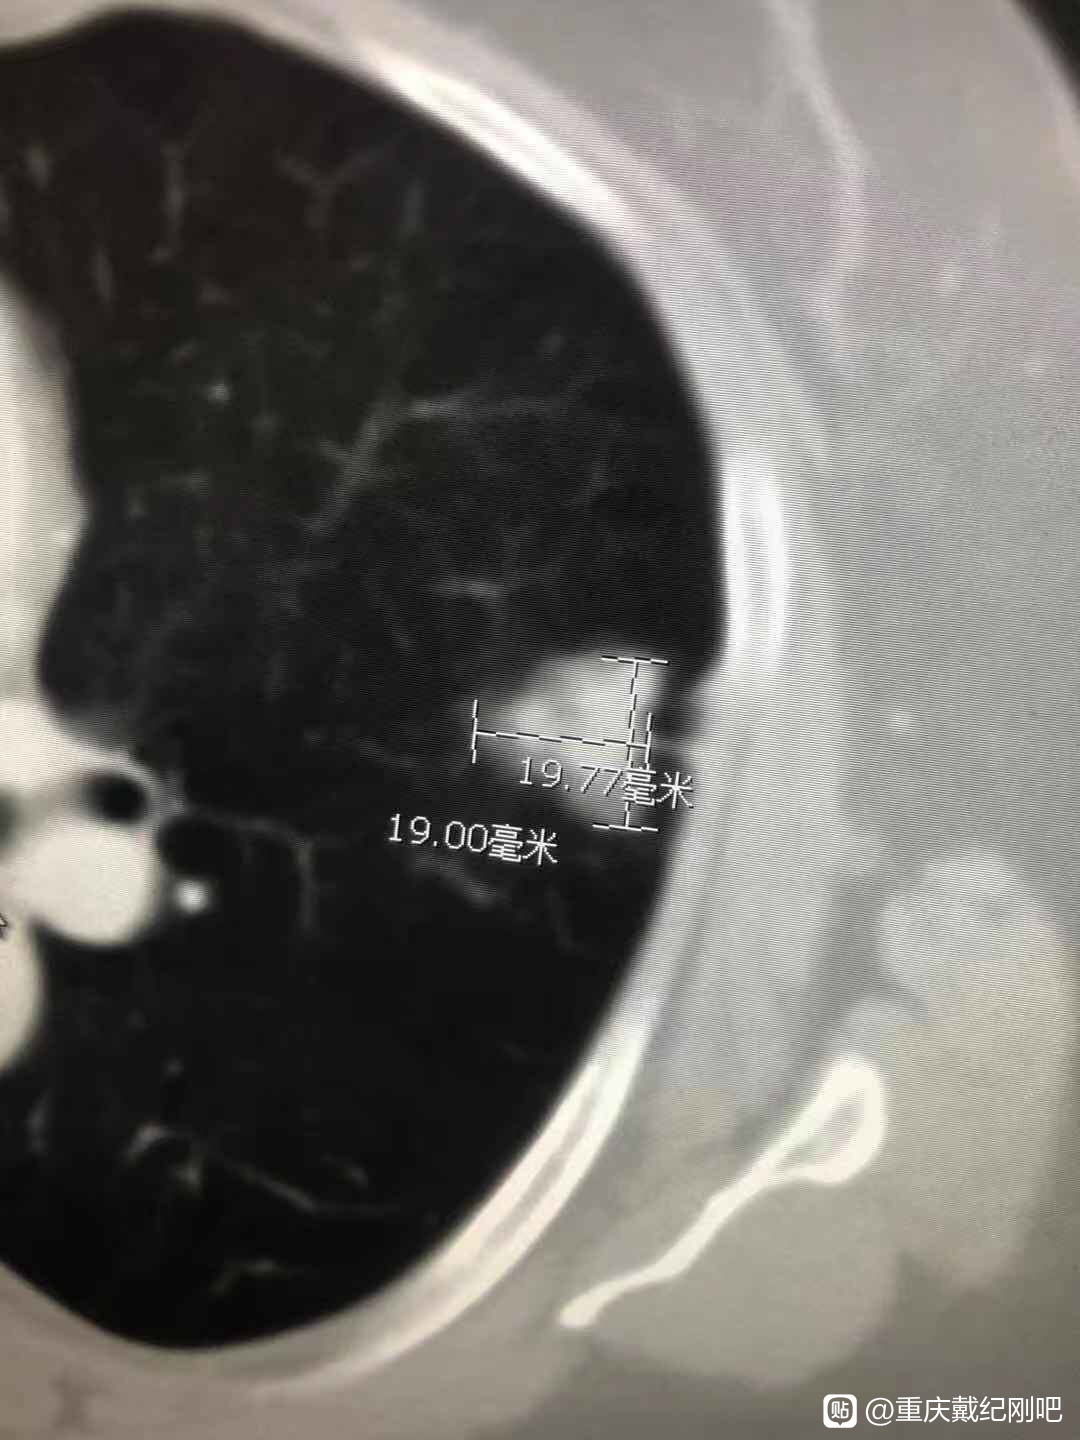

命运真的太不公平了,脑出血的爸爸植物人状态卧床两年多,全家人特别是妈妈24小时不离地照顾了两年多。2020年6月份,妈妈体检做了个CT,医生说妈妈肺上有两个结节,需要做穿刺诊断是恶性还是良性。

结果让我和弟弟真的大吃一惊,妈妈被查出肺腺癌,而且是晚期,不能手术。

基因检测可以做一个,选一个最便宜,3000-4000的基因检测套餐做即可。而且,您母亲这个不一定就是晚期肺癌,很可能是多原发早期肺癌。